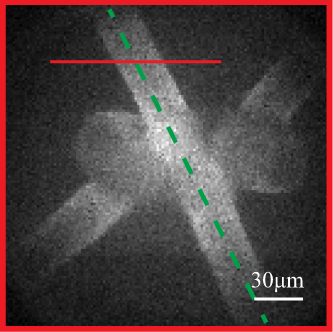

Laforest T., Künzi M., Kowalczuk L., Carpentras D., Behar-Cohen F. and Moser C. , Transscleral optical phase imaging of the human retina, Nature Photonics, March 2020. |

Laforest T., Künzi M., Kowalczuk L., Carpentras D., Behar-Cohen F., Moser C., Transscleral Optical Phase Imaging of the Human Retina – TOPI, pre print, May 15th, 2019. |

Laforest T., Carpentras D., Kunzi M., Kowalczuk L., Behar-Cohen F., Moser C., A new microscopy for imaging retinal cells, arXiv:1712.08472. |

Kowalczuk L., Dornier R., Kunzi M., Iskandar A., Misutkova Z., Gryczka A., Navarro A., Jeunet F., Mantel I., Behar-Cohen F., Laforest T., Moser C., in vivo Retinal Pigment Epithelium Imaging using Transscleral OPtical Imaging in healthy eyes, Ophthalmology Science, 100234 (2022). |

Govindahari V., Dornier R., Ferdowsi S., Moser C., Mantel I., Behar-Cohen F., Kowalczuk L., High-Resolution Adaptive Optics-Trans-scleral Flood Illumination (AO-TFI) Imaging of Retinal Pigment Epithelium (RPE) in Central Serous Chorioretinopathy (CSCR), Scientific Reports, 14.1 (2024):13689. doi: 10.1038/s41598-024-64524-4. |

|

Kowalczuk L., Dornier R., Navarro A., Jeunet F., Moser C., Behar-Cohen F., Mantel I., Adaptive Optics-Transscleral Flood Illumination Imaging of Retinal Pigment Epithelium in Dry Age-Related Macular Degeneration, Cells (2025), 14(9), 633. doi: 10.3390/cells14090633. |